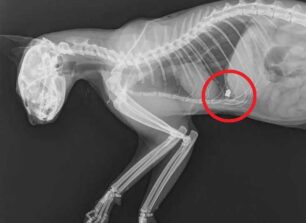

Μια αδέσποτη γάτα πυροβολημένη με αεροβόλο εντόπισε στις 3 Ιουνίου η Κυριακή Λυκουρέση την περιοχή του Περιστερίου Αττικής στη οδό Σουρή. Η γάτα μόλις εντοπίστηκε. Το ζώο σερνόταν και η κα Λυκουρέση αφού το έπιασε…διαβάστε περισσότερα